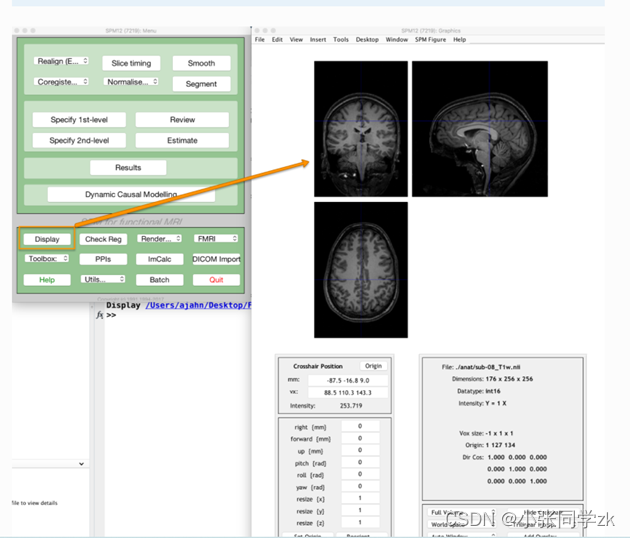

在MATLAB的命令窗口行输入 spm fmri

按照下图,点击Display,同样功能像也可以这样加进去,我们还可以看每个被试的时间序列信息

观察功能像: